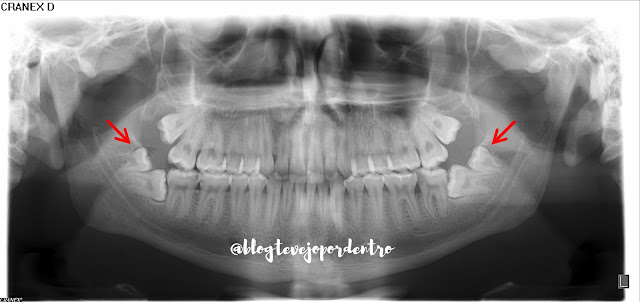

Quartos molares